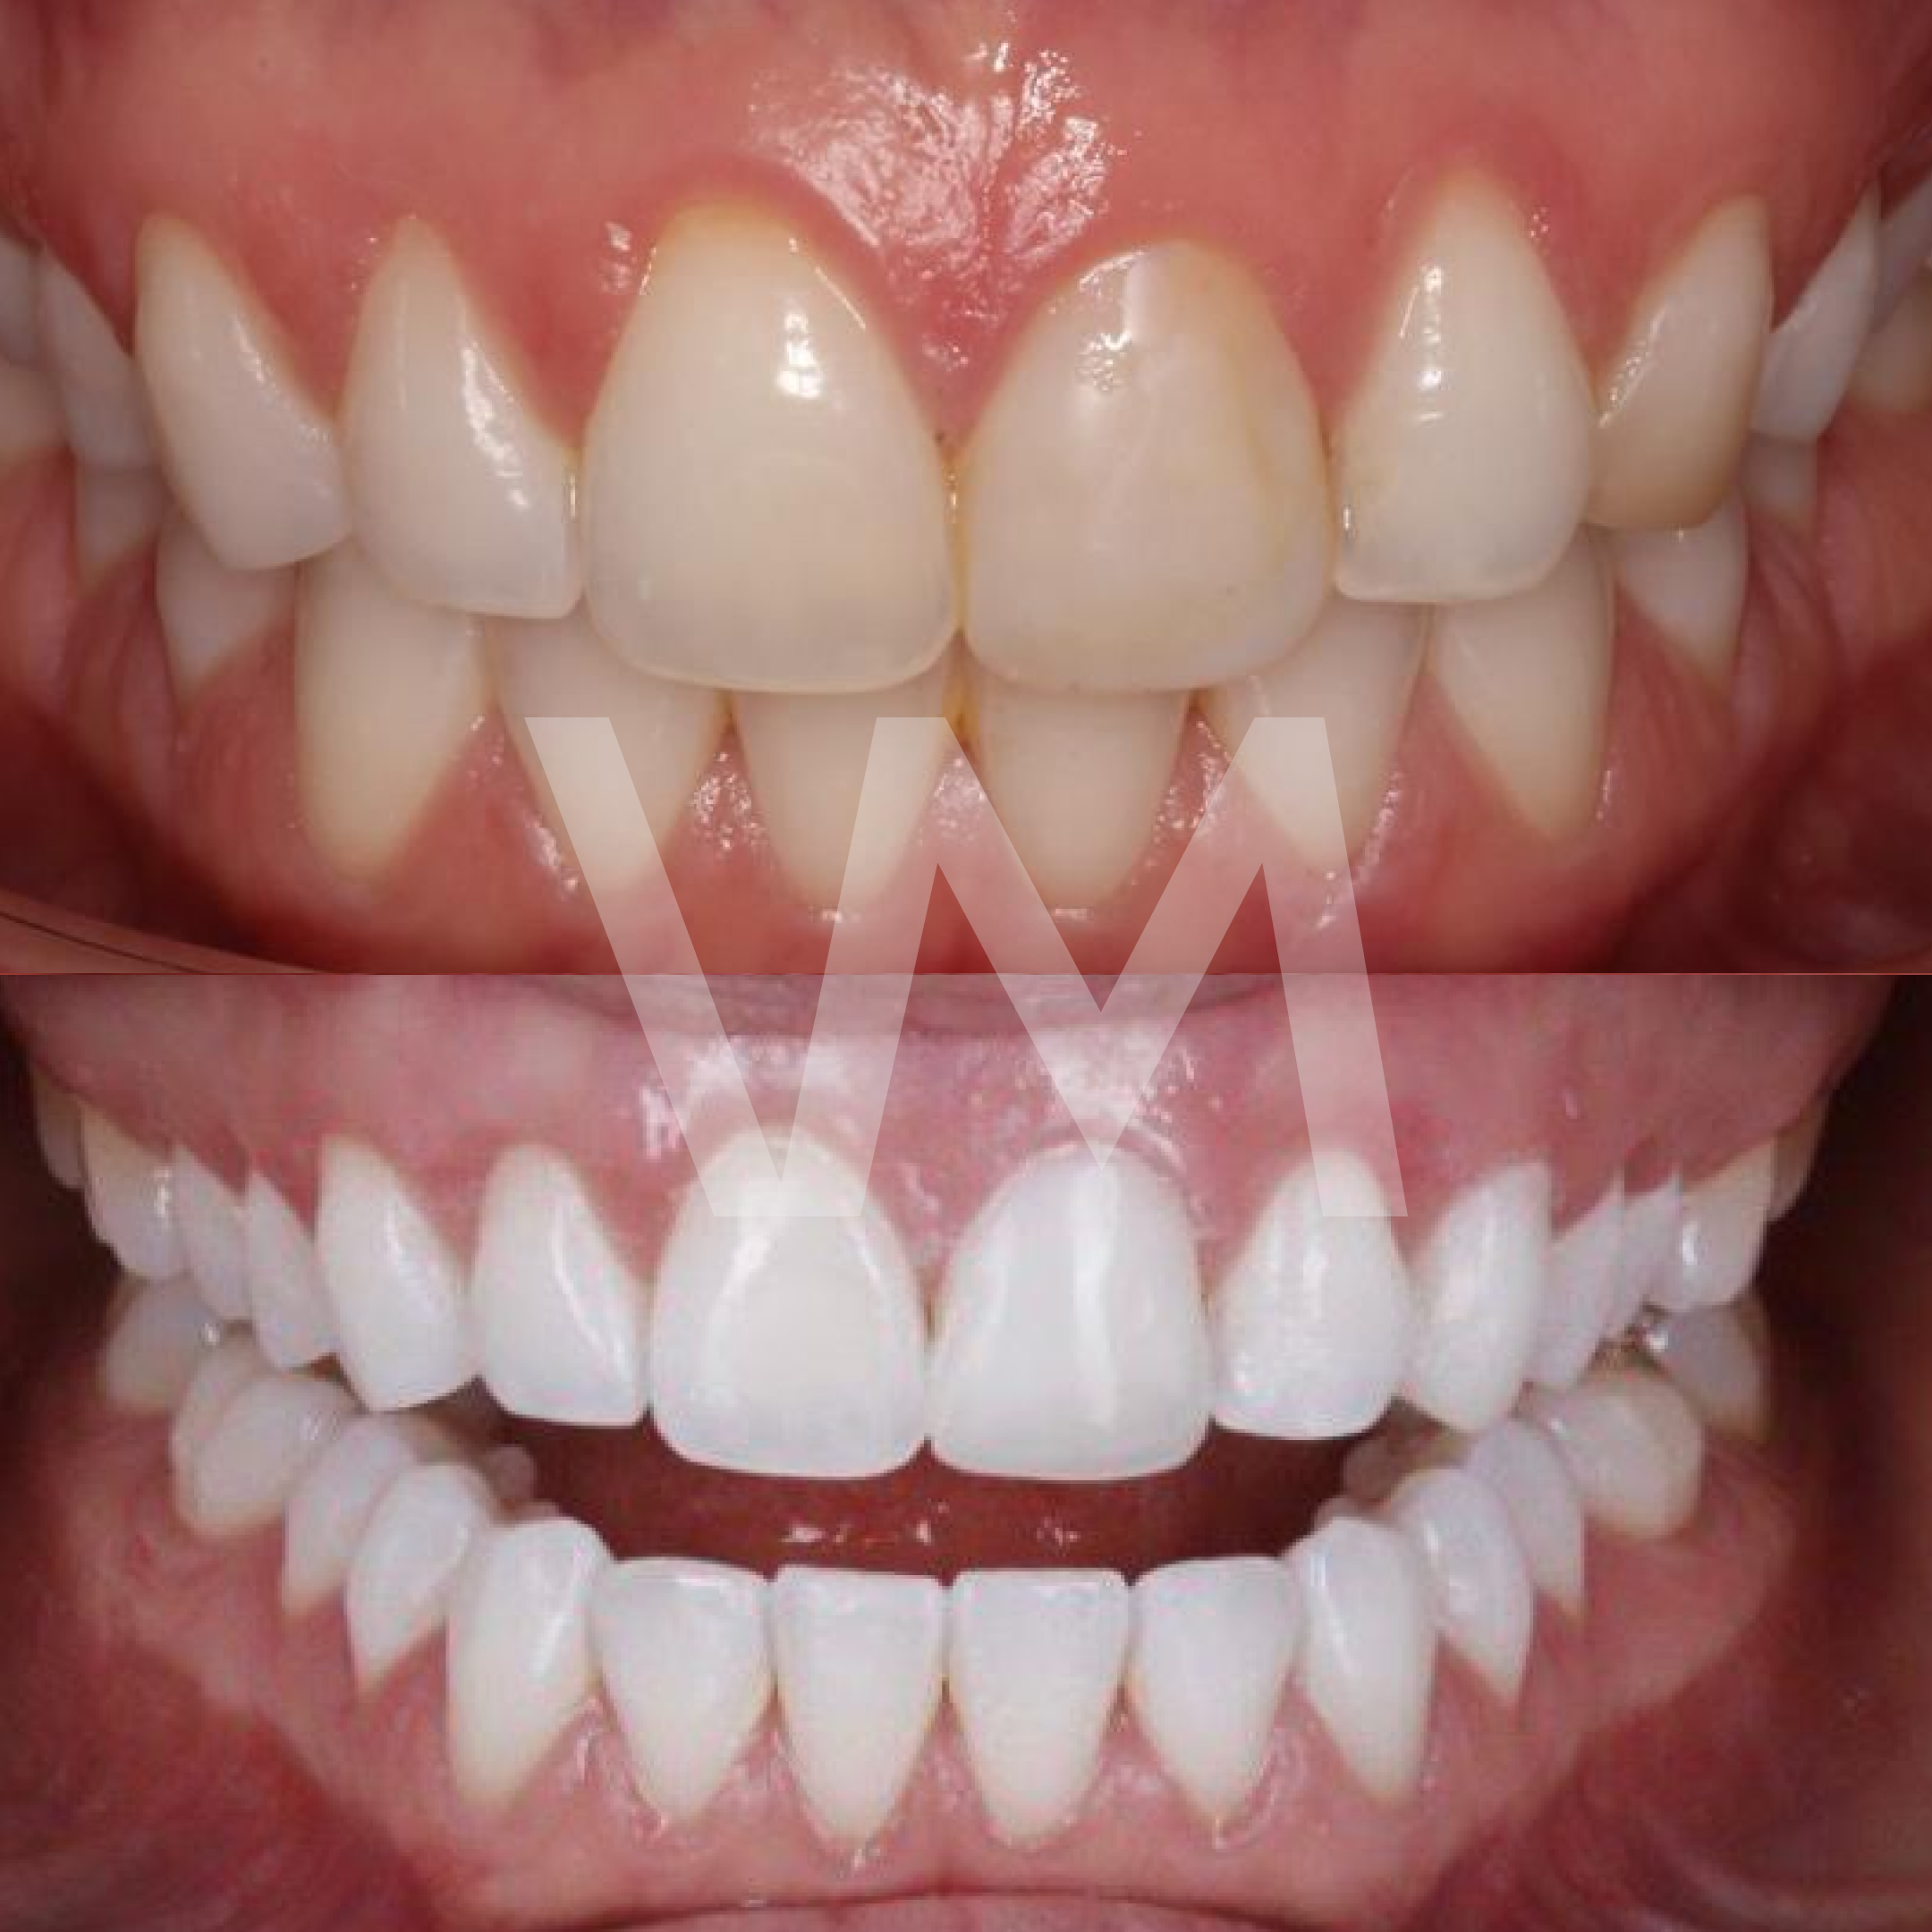

Injertos de encía

Cirugías de Injertos de Encía del Paladar e Injertos Sintéticos para el Tratamiento de Recesiones Gingivales

Las recesiones gingivales son un problema común en el que las encías retroceden, dejando expuesta la raíz del diente y aumentando el riesgo de sensibilidad dental, deterioro del hueso y pérdida de dientes. Para corregir estas recesiones y restaurar la salud gingival, se pueden realizar cirugías de injertos de encía del paladar e injertos sintéticos.

Beneficios de las Cirugías de Injertos de Encía:

- Mejora la salud gingival y previene la progresión de la recesión gingival.

- Reduce la sensibilidad dental causada por la exposición de la raíz del diente.

- Mejora la estética de la sonrisa al restaurar el contorno gingival natural.

Las cirugías de injertos de encía del paladar e injertos sintéticos son procedimientos efectivos para el tratamiento de recesiones gingivales, restaurando la salud y la estética de las encías y mejorando la calidad de vida del paciente.

Casos clínicos realizados por la Dra. Paulina